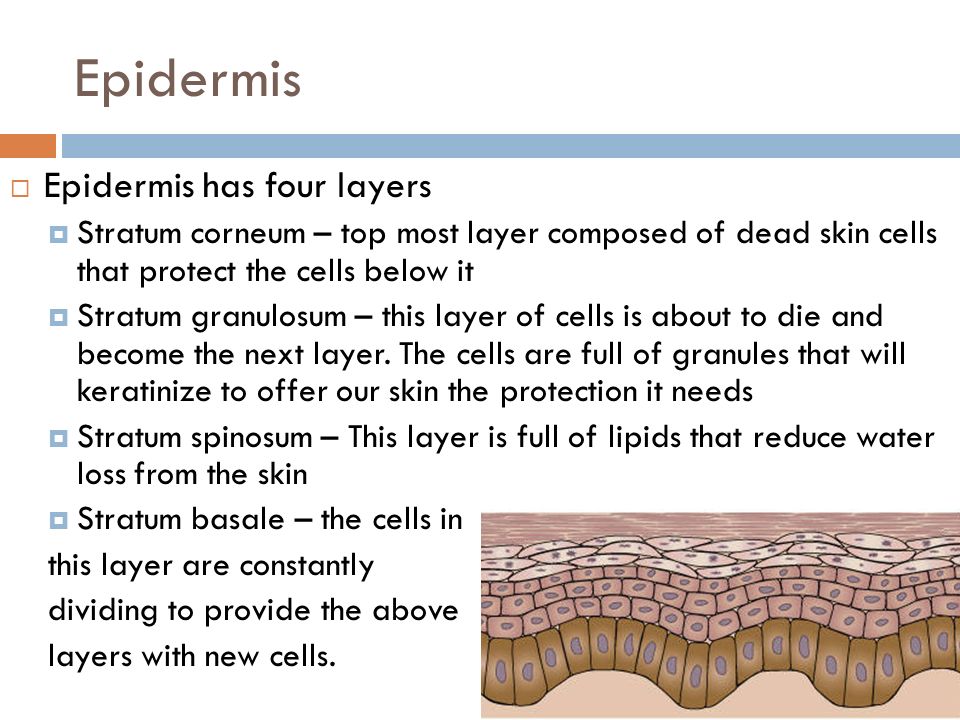

7. The Excretory System (human)

- Excretory organs and their functions e.g. kidney, skin and lungs.

- The process of excretion.

- Waste materials of excretion e.g. carbon (iv) oxide, sweat and urine.